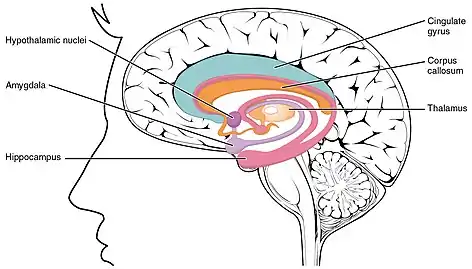

![]() Hippocampus (lowest pink bulb) as part of the limbic system | |

Relation to limbic system

The term limbic system was introduced in 1952 by Paul MacLean[15] to describe the set of structures that line the deep edge of the cortex (Latin limbus meaning border): These include the hippocampus, cingulate cortex, olfactory cortex, and amygdala. Paul MacLean later suggested that the limbic structures comprise the neural basis of emotion. The hippocampus is anatomically connected to parts of the brain that are involved with emotional behavior – the septum, the hypothalamic mammillary body, and the anterior nuclear complex in the thalamus, and is generally accepted to be part of the limbic system.[16]